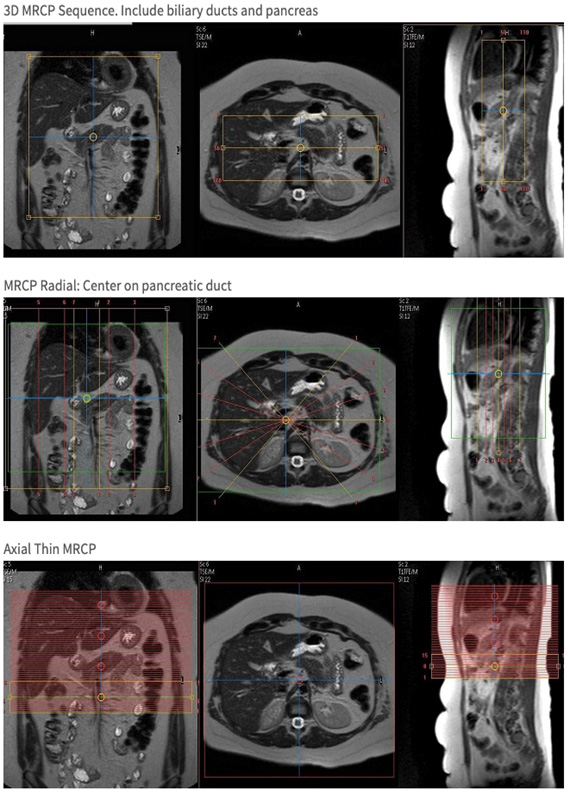

From www.svuhradiology.ie

MRCP Radiology at St. Vincent's University Hospital What Is A Mri With Mrcp Mrcp stands for magnetic resonance cholangiopancreatography. It uses magnetic resonance imaging to visualize the biliary and pancreatic. A magnetic resonance cholangiopancreatography (mrcp) scan is a medical scanning method that uses radio waves and a magnetic field to. Mri stands for magnetic resonance imaging. Magnetic resonance cholangiopancreatography (mrcp) is a special type of mri that uses computer software to image the. What Is A Mri With Mrcp.

From www.mriclinicalcasemap.philips.com

Liver with MRCP Philips MR Body Map What Is A Mri With Mrcp A magnetic resonance cholangiopancreatography (mrcp) scan is a medical scanning method that uses radio waves and a magnetic field to. Mri stands for magnetic resonance imaging. Magnetic resonance cholangiopancreatography (mrcp) is a special type of mri that uses computer software to image the pancreatic and bile ducts, areas where tumors. What is mrcp scan used for? Mrcp is a type. What Is A Mri With Mrcp.

From www.ohsu.edu

MR Liver Mass with MRCP WO BODY Protocol OHSU What Is A Mri With Mrcp Mrcp is a type of. What is mrcp scan used for? Mrcp is a type of magnetic resonance imaging (mri) scan. Magnetic resonance cholangiopancreatography (mrcp) is a medical imaging technique. Mrcp stands for magnetic resonance cholangiopancreatography. It uses strong magnetic fields and radio waves to produce an image of your internal organs. Mri stands for magnetic resonance imaging. A magnetic. What Is A Mri With Mrcp.